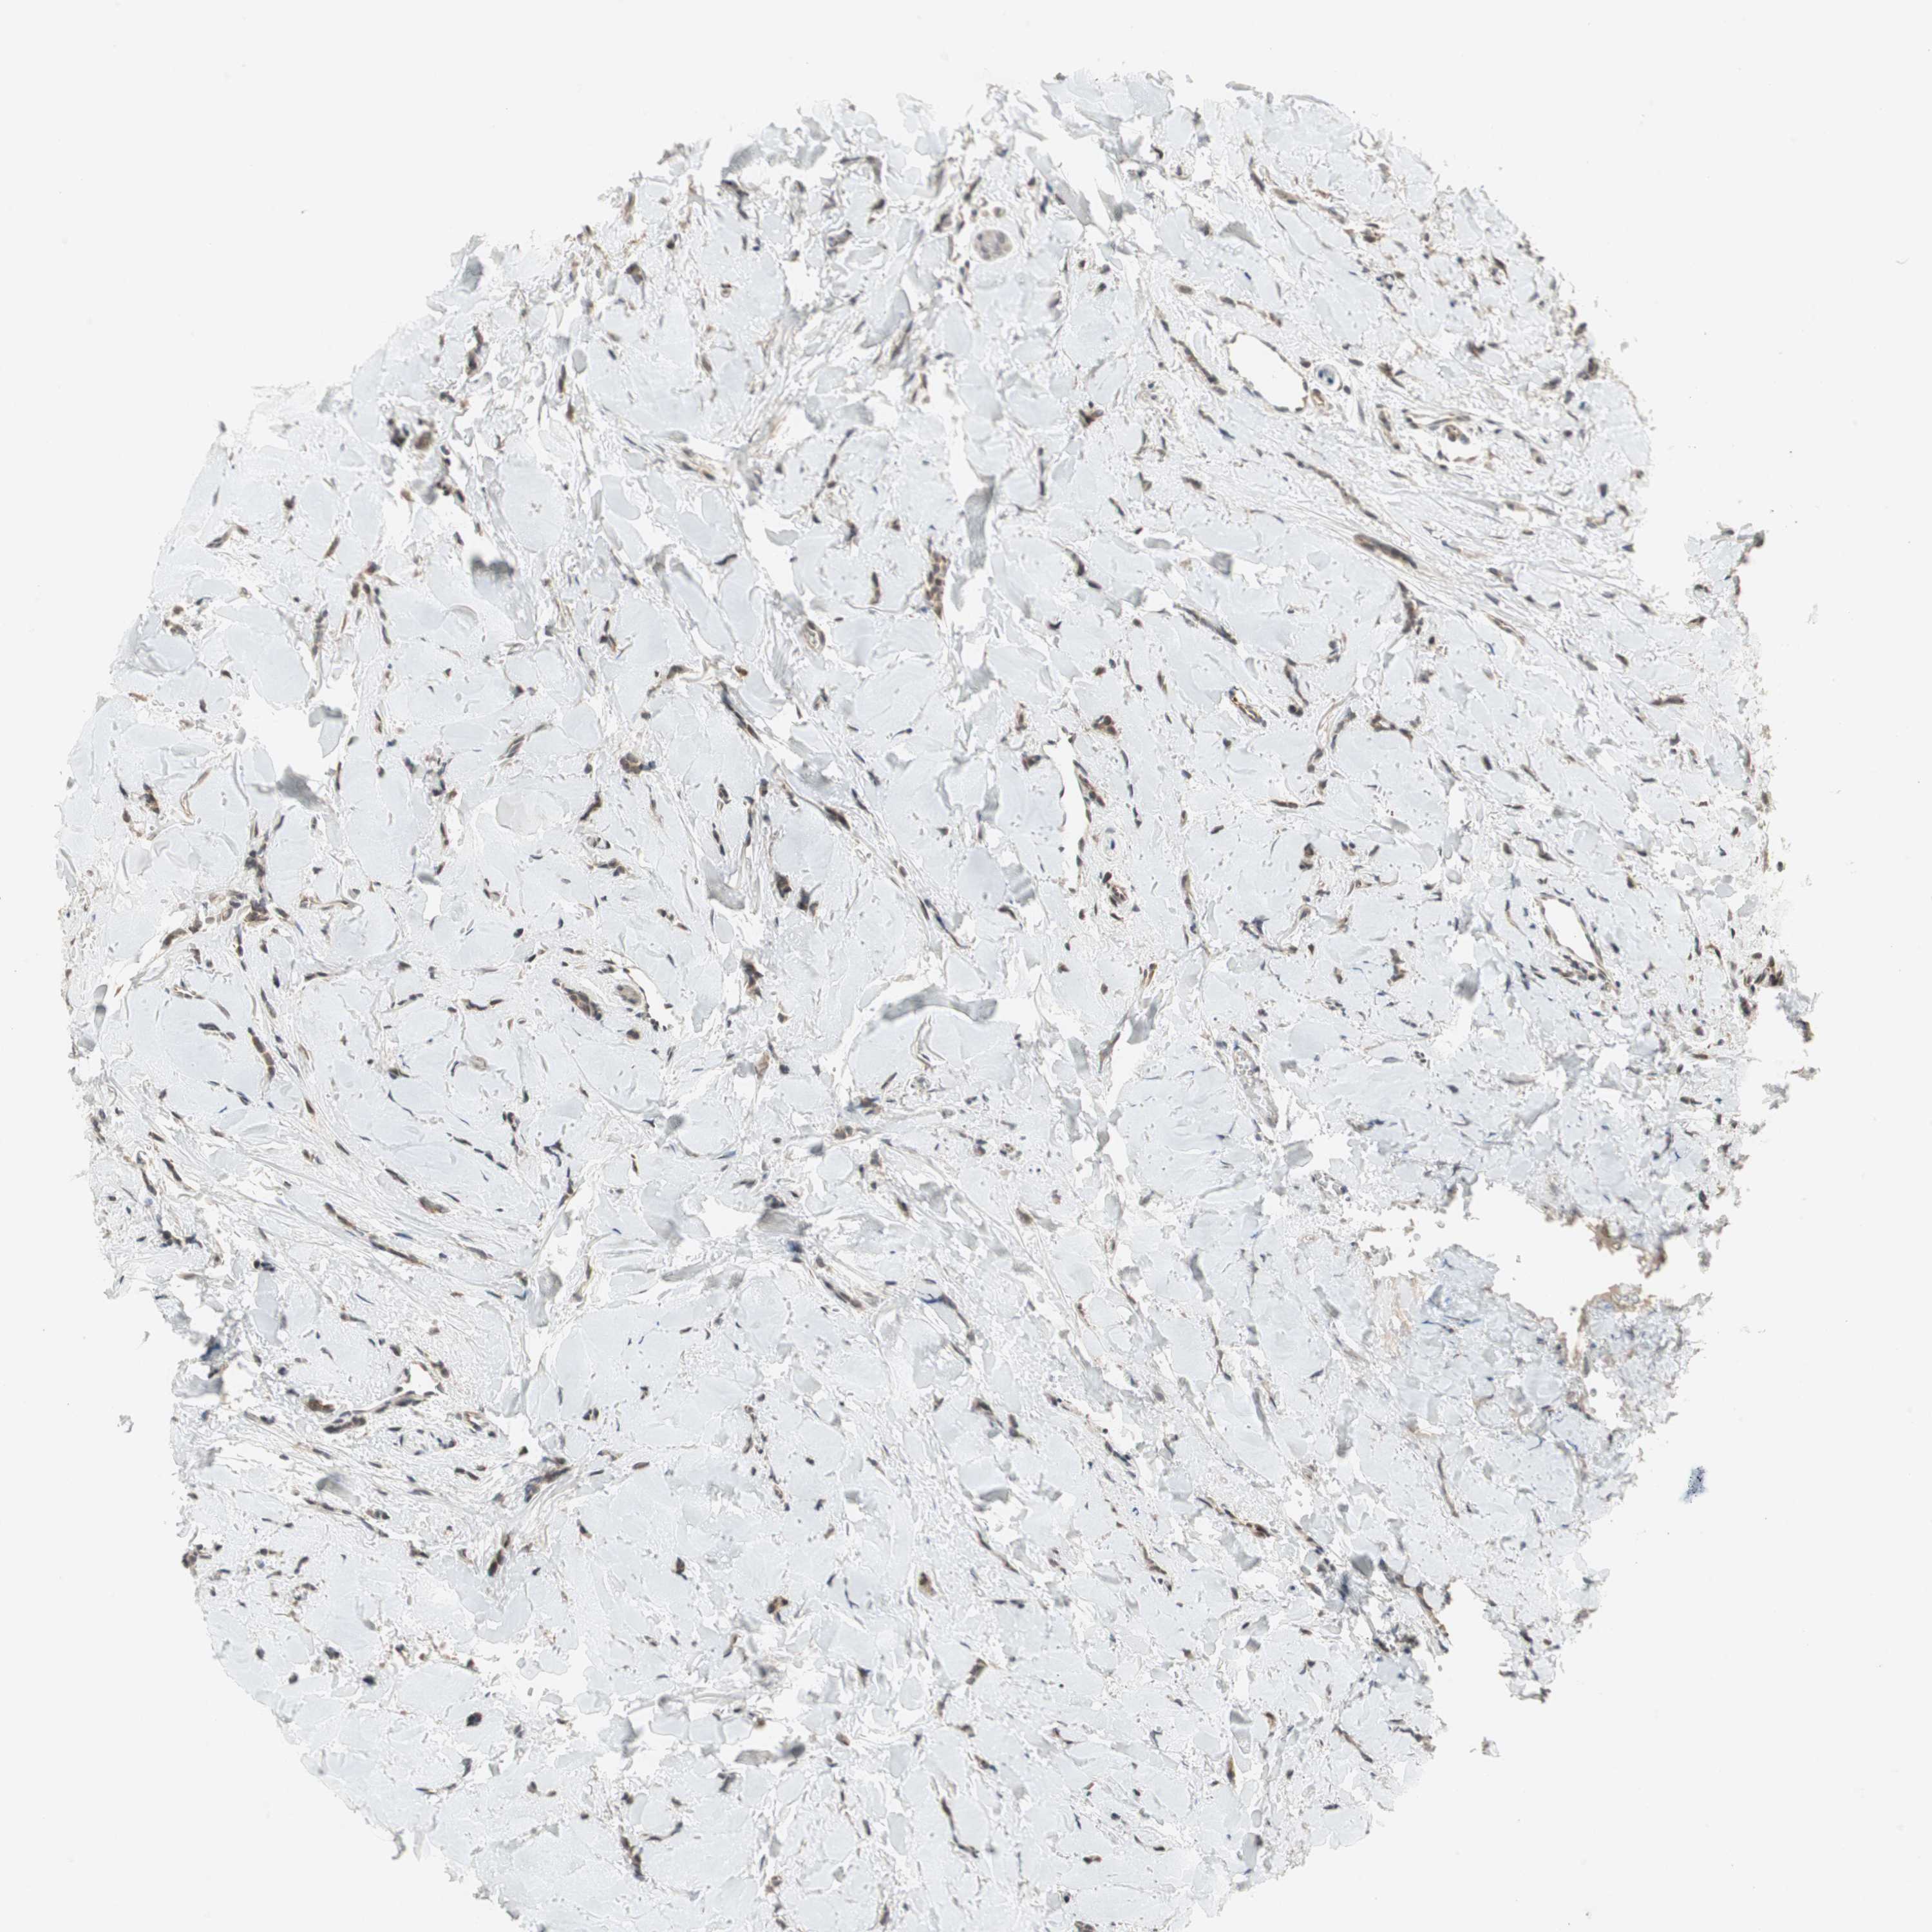

CANCER BREAST CANCER Show tissue menu

BRCA TCGA BRCA VALIDATION PROTEIN EXPRESSION

ANTIBODIES